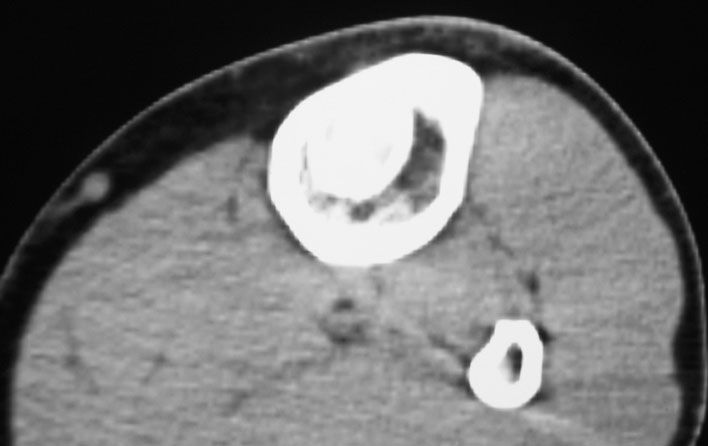

标题: CT19885:左胫骨上端肿瘤。 [打印本页]

标题: CT19885:左胫骨上端肿瘤。

男,20岁,医学院学生,11年前感左胫骨上端劳累后酸痛,曾由父母带到国内好几家有名望的医院诊治,但众说不一,所以基本上没有治疗。今年三月又开始出现症状,又到多家省级医院求治,但专家们的意见还是不能统一。各生化检查正常。mri考虑到胫骨上端良性血管瘤可能性大。ct考虑纤维瘤可能性大。请各位发表高见。

考虑胫骨多发性内生骨瘤。

胫骨多发性内生骨瘤可能。

考虑左胫骨良性骨肿瘤或骨肿瘤样病变(多发性内生骨瘤?骨纤维结构不良?)。

考虑胫骨多发性内生骨瘤可能。应该传骨窗。

考虑左胫骨良性骨肿瘤或骨肿瘤样病变(多发性内生骨瘤?骨纤维结构不良?)。骨梗死,纤维瘤。